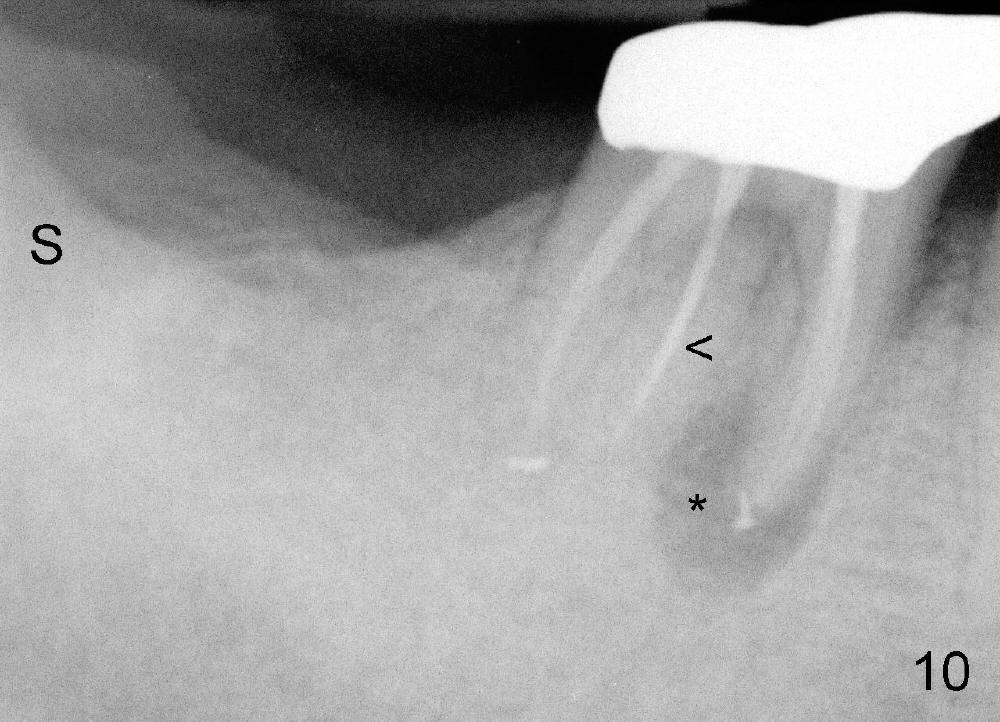

五十来岁郑先生缺失两个下颌第二磨牙,严重牙齿磨耗,三年前主诉右下第一磨牙冷热痛(可能与磨耗有关),近中有轻度根尖阴影(图一箭头),初步CT检查表明该牙齿有四个根管(图二,三),兴高采烈,这样不会错过远中舌侧根管(DL),开髓发现根管几乎阻塞,尤其是远中舌侧,hand files不容易进入根尖,使用20/.04 rotary file时,在根尖断裂(图四箭头,其余根管插入30/.06牙胶尖),一时不能bypass断针,暂封。十二天后,重新bypass断针,终于成功,但是取不出断针,扩大二十号hand file(远中舌侧根管),图五,图六侧方充填(lateral condensation)之前,图七之后(图六,七*:近中阴影)。根管治疗和牙冠之后一直无症状,一年半在第二磨牙处植牙(图八I),虽然第一磨牙近中根尖阴影增大(*),但离植牙还有一定距离,可能不会产生问题。不过不久植牙松动,病人自己取出,可能当时钻洞太大,而不够深(no primary stability),怕侵犯下颌神经(图八红线)。十个月后再次试图植牙(图九D:钻头),突然发现智齿(阻生)在手术视野之中,而且智齿咬合面不干净,结果取消植牙,把智齿拔除,这时病人第一磨牙仍没有症状,但是根尖阴影不可观(图九*),远中舌侧根尖好像没有病变(箭头)。大概这次智齿拔除也与左下智齿七拔除(左下第二磨牙植牙之前)一样不舒服,郑先生一直没有回来做右下第二磨牙植牙。上周六他终于登门,右下第一磨牙出现根尖脓肿症状(术后近三年),根尖片如图十。S代表已经愈合智齿牙槽窝,根尖阴影不小,断针根尖仍没有阴影。